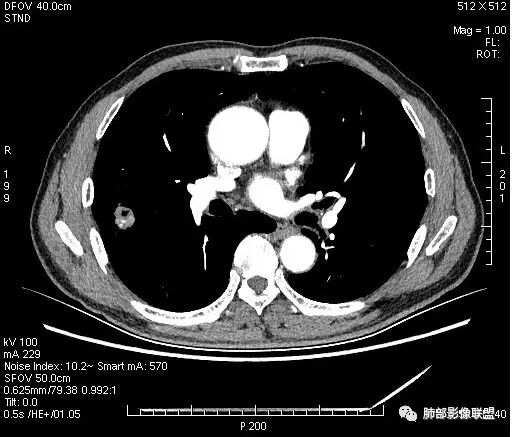

影像学改变:

1.右肺上叶后段类圆形结节影,密度不均,有坏死空洞,坏死比较彻底,内外壁都较清楚。

4.病灶轻到中度强化。病灶内血管走行较完好,病灶旁血管局部显示粗大。

5.支气管关系不确定。

6.灶周见小结节影(卫星灶),边界不甚清晰。

会是肿瘤吗?

1.病灶整体太圆,没有深分叶,没有粗短毛刺,收缩明显乏力,强化不显著等等缺乏典型肺腺癌的影像学特征。腺癌如此小病灶出现空洞更是匪夷所思!

2.肺鳞癌易坏死,可病灶如此小即出现影像学上可见的彻底的坏死空洞也非常少见。

病灶内“旁若无人”的血管走形也让人难以理解。而该疑问也存在于结核病灶的辨析当中。